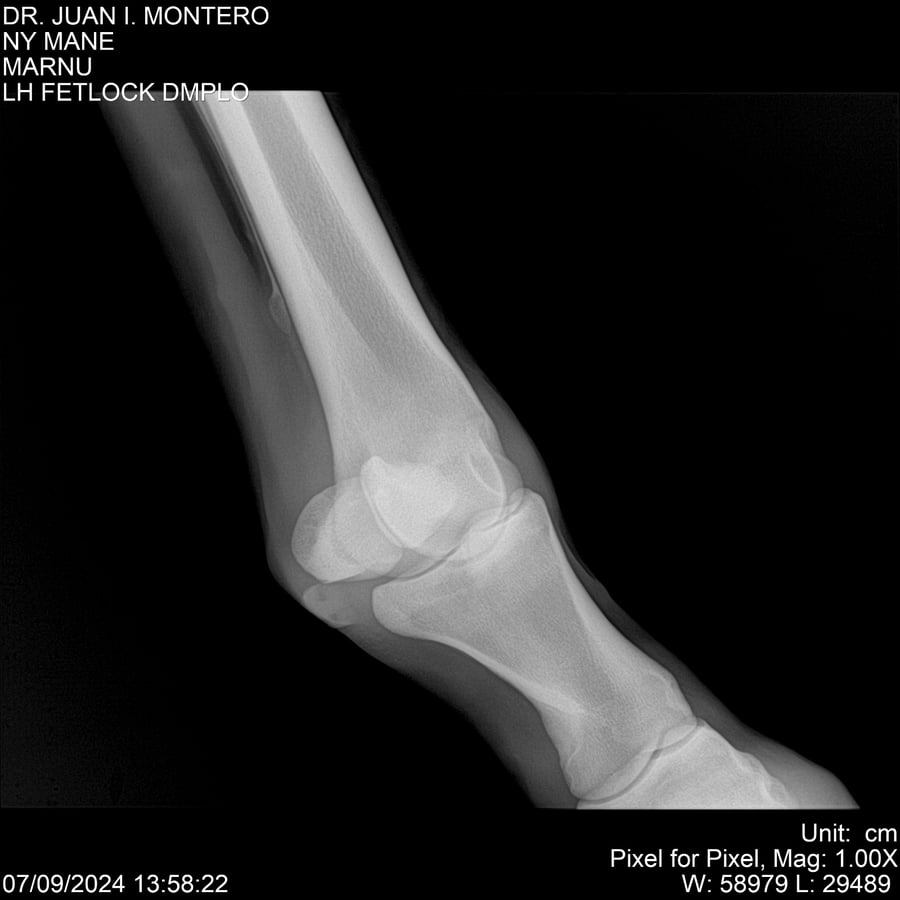

LOTE 20, NY MANE Lote Anterior Volver al remate Lote Siguiente Ficha Contacto Montevideo - Ficha del Lote Identificador: #282520 Categoría: Yeguarizos 76 Visualizaciones ClicData Contacto Empresa: Abelenda N. R., Walter Hugo Nombre*: Teléfono* : E-mail* : Mensaje Enviar Registrese gratis Este contenido Exclusivo está disponible sólo para usuarios registrados Ingresar